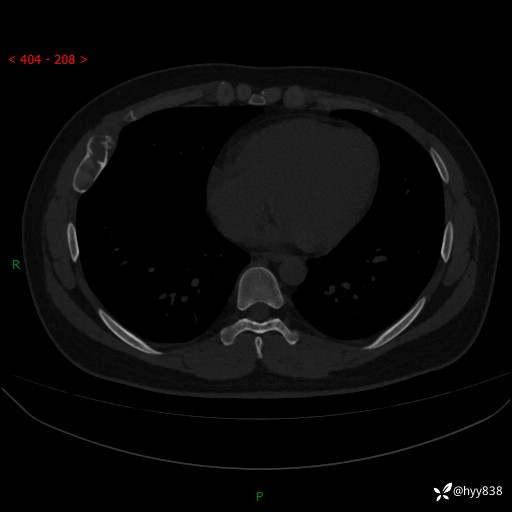

年轻小伙,右侧胸部疼痛4天余。病理科说肯定不是骨纤,那是啥---结果公布~

性别:男

年龄:24岁

主诉:右侧胸部疼痛4天余。

现病史:患者约4天前突发右侧胸部疼痛,无瘙痒,无头痛、头晕,无心慌、胸闷、呼吸困难、咳嗽、咳痰、咯血,无腹痛、腹胀等不适,未作进一步诊治。于2024年5月外院行胸部CT平扫示右侧肋骨骨质改变。现为求进一步治疗,遂于我院就诊。门诊以“胸壁肿物”收入我科。 患者自起病以来,精神可,睡眠可,饮食可,大小便正常,体重无明显改变。

胸部CT平扫